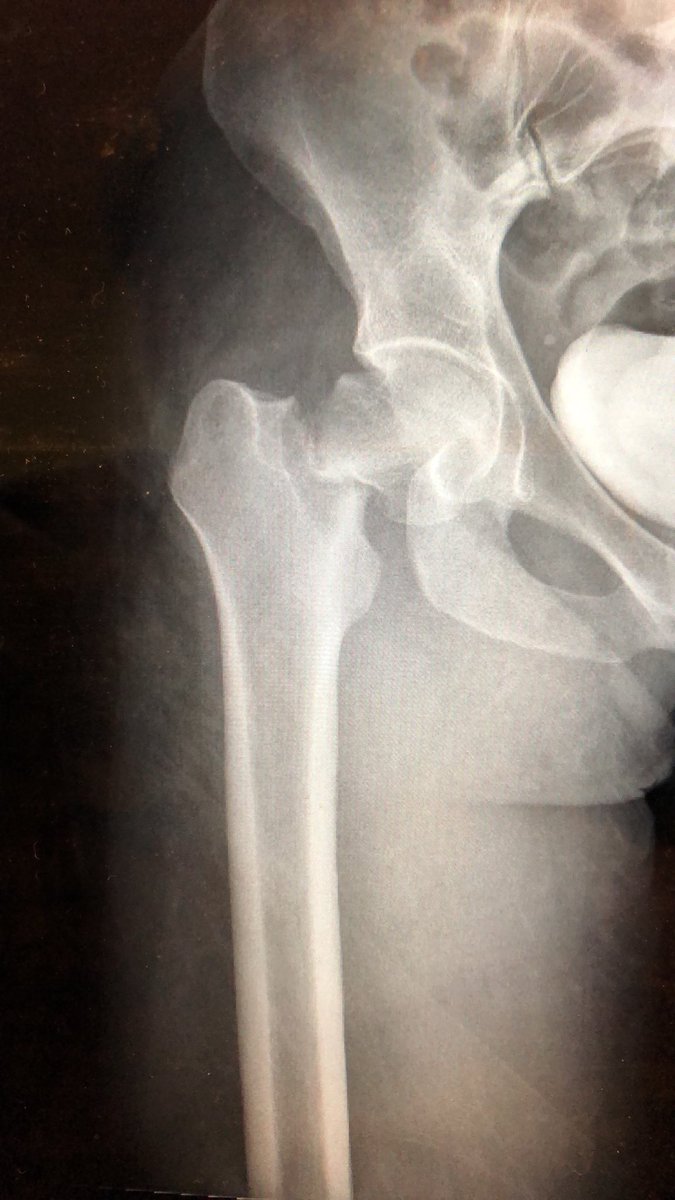

Just a little midnight fun when not on call #orthotrauma #HopkinsOrtho #femoralneckfracture #openreduction #SmithPetersen #lifeinthetimeofcovid19 #fns